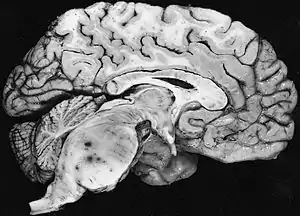

Diffuse fibrillary astrocytomas arising in the brain stem favor the pons: The tumor here produces the classic hypertrophy of the affected region.

Fibrillary astrocytomas arise from neoplastic astrocytes, a type of glial cell found in the central nervous system. They may occur anywhere in the brain, or even in the spinal cord,[1] but are most commonly found in the cerebral hemispheres. As the alternative name "diffuse astrocytoma" implies, the outline of the tumour is not clearly visible in scans, because the borders of the neoplasm tend to send out tiny microscopic fibrillary tentacles that spread into the surrounding brain tissue. These tentacles intermingle with healthy brain cells, making complete surgical removal difficult. However, they are low-grade tumors, with a slow rate of growth, so patients commonly survive longer than those with otherwise similar types of brain tumours, such as glioblastoma multiforme.[1]